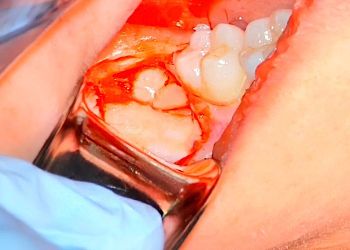

FLAP DESIGN

Learn how to design, elevate, and reflect flaps with confidence—master the essential techniques that drive successful third-molar surgery.